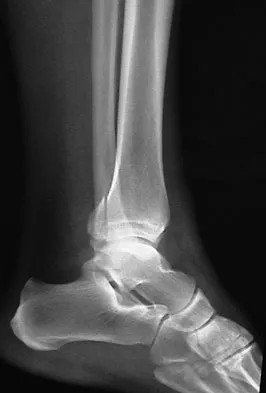

A 57-year-old man has had right ankle pain for the past 10 months following an injury that went untreated. Radiographs are shown in Figures 30a through 30c. Management should consist of

The radiographs reveal a malunited distal fibular fracture with shortening. Because there appears to be an adequate cartilage space within the ankle joint, the role of reconstruction would be to prevent arthrosis and the need for ankle arthrodesis, as well as to decrease symptoms. The treatment of choice is restoration of fibular length, alignment, and rotation with osteotomy plating, and bone grafting as needed. There is no indication for ligament reconstruction of a mechanically stable ankle, and tibial shortening osteotomy will not assist in correcting the deformity. Cast immobilization may assist with improvement of symptoms but will not correct the overall process. Determination of fibular length is best done by comparing the talocrural angle of the injured side with the uninjured side. The goal is to perfectly reduce the talus in the ankle mortise. Marti RK, Raaymakers EL, Nolte PA: Malunited ankle fractures: The late results of reconstruction. J Bone Joint Surg Br 1990;72:709-713. Geissler W, Tsao A, Hughes J: Fractures and injuries of the ankle, in Rockwood CA Jr, Green DP, Bucholz RW, Heckman JD (eds): Rockwood and Green's Fractures in Adults, ed 4. Philadelphia, PA, Lippincott-Raven, 1996, pp 2201-2206.